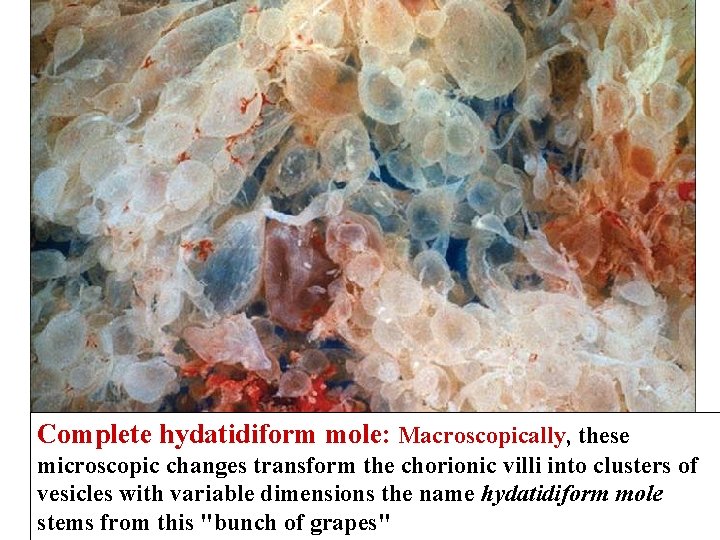

Complete hydatidiform mole: Macroscopically, these microscopic changes transform the chorionic villi into clusters of vesicles with variable dimensions the name hydatidiform mole stems from this "bunch of grapes"